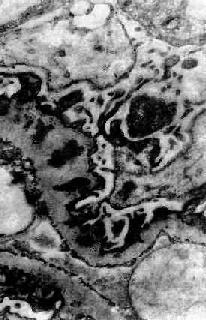

图12-19 膜性肾小球肾炎 电镜下见肾小球毛细血管基底膜增厚,电子致密沉积物被增生的基底膜包围并埋藏于基底膜内 肾小球毛细血管损伤,通透性显著增加,大量蛋白由肾小球滤过进入肾小管,部分被肾小管再吸收。近曲小管上皮细胞浊肿,胞浆内常有玻璃样变颗粒和大量脂肪空泡。晚期随肾小球病变加重,肾小管也萎缩。间质纤维组织增生,炎性细胞浸润较少。 肉眼观,早期可见肾肿胀,体积增大,色苍白。切面皮质明显增宽,髓质无特殊变化。晚期,肾体积缩小,表面呈细颗粒状。 【临床病理联系】 膜性肾小球肾炎是引起肾综合征最常见的原因之一。成人肾病综合征由膜性肾小球肾炎引起者约占40%,小儿仅占5%。膜性肾小球肾炎时,肾小球基底膜严重损伤,通透性显著增加,大量蛋白包括大分子蛋白都可由肾小球滤过引起严重的非选择性蛋白尿。由于大量蛋白由尿中排出,血浆蛋白降低,引起低蛋白血症,血浆胶体渗透压降低,血管内液体渗入组织间隙,引起水肿。同时血容量减少,肾小球血流量和肾小球滤过减少,醛固酮和抗利尿激素分泌增加,引起水钠潴留,进一步加重水肿。因此水肿很严重,往往为全身性,以眼睑和身体下垂部分最明显,严重者并可有胸水和腹水。 高脂血症的原因还不很清楚,可能由于低蛋白血症刺激肝合成各种血浆蛋白包括脂蛋白增多,因此病人有高脂血症和高胆固醇血症。由于血脂过高,血浆内的脂蛋白也可由肾小球滤过,引起脂尿症。 膜性肾小球肾炎时,肾小球内无明显增生和炎症现象。早期,毛细血管不狭窄,血流通畅,故血尿不多见,血压不高,无明显氮质血症。晚期,毛细血管阻塞,肾小球硬化,可引起高血压和肾功能衰竭。 【结局】 膜性肾小球肾炎起病缓慢,病程较长。病变轻者,症状可消退或部分缓解。多数则反复发作,对皮质激素治疗效果不显著。发展到晚期,大量肾单位纤维化、硬化,可导致肾功能衰竭和尿毒症。